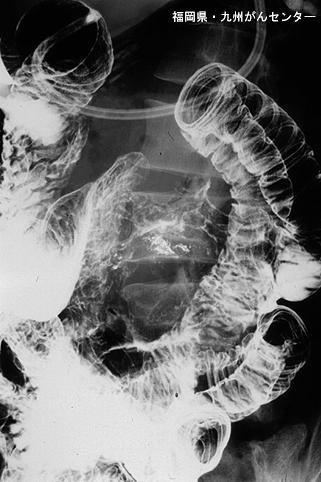

Posted by: Fukuoka Pref., 九州癌中心

疾病(病理主体)的分类转移性肿瘤/

部位(按器官分)小肠/空肠

检查方法X线

肿瘤最大直径40以上